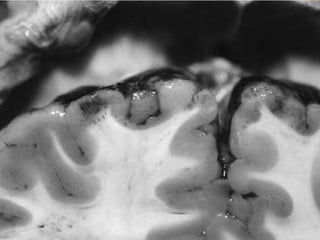

mli1. Evidence of application of blunt force. Accidental Homicidal Suicidal – Unusual ARTIFICIAL BRUISES 2. Though in itself a trivial injury, Lies in the site & the organs involved. Contusion of vital organs heart and brain.Caused marked derangement of functions & even death

3. Volume of blood- Circulating Diminished – Due to Extravasation4. Patterned Bruising Nature of agent used.5. Healing – Determination of age.6. Bruising- Scalp- It is better. 7. Bruising over the particular part of the body-Indicate some peculiar offence Ex : On the Neck Inner Side of Thigh – FemalesIndicate Sexual Assault    small bruises The so called “six Penny Bruises”8.Character & manner of injury may be known from its distribution.

complications1. Contusion contain 20- 30 ml of blood or even more. Multiple contusion can cause death from shock & internal haemorrhages.2. Gangrene & death of tissue.3.Good site for Bacterial growth.

mli1. Evidence ofapplication of blunt force. Accidental Homicidal Suicidal – Unusual ARTIFICIAL BRUISES 2. Though in itself a trivial injury, Lies in the site & the organs involved. Contusion of vital organs heart and brain.Caused marked derangement of functions & even death

3. Volume ofblood- Circulating Diminished – Due to Extravasation4. Patterned Bruising Nature of agent used.5. Healing – Determination of age.6. Bruising- Scalp- It is better. 7. Bruising over the particular part of the body-Indicate some peculiar offence Ex : On the Neck Inner Side of Thigh – FemalesIndicate Sexual Assault small bruises The so called “six Penny Bruises”8.Character & manner of injury may be known from its distribution.

complications1. Contusion contain20- 30 ml of blood or even more. Multiple contusion can cause death from shock & internal haemorrhages.2. Gangrene & death of tissue.3.Good site for Bacterial growth.